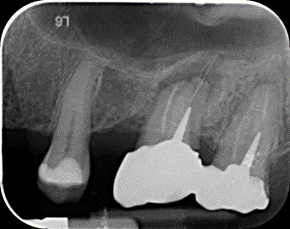

En cas d’échec, (persistance d’une lésion inflammatoire osseuse), et après un suivi radiographique approprié, un retraitement endodontique ou une chirurgie pourront éventuellement être envisagés pour toujours tenter de conserver la dent. Malgré nos efforts, environ 5 à 10% des traitements endodontiques peuvent se solder par un échec, et dans ce cas, la dent concernée devra être extraite.

Cependant, lorsque le traitement endodontique est jugé impossible voire trop complexe pour permettre une longévité suffisante de la dent, le traitement implantaire reste l’un des traitements de choix à suivre.